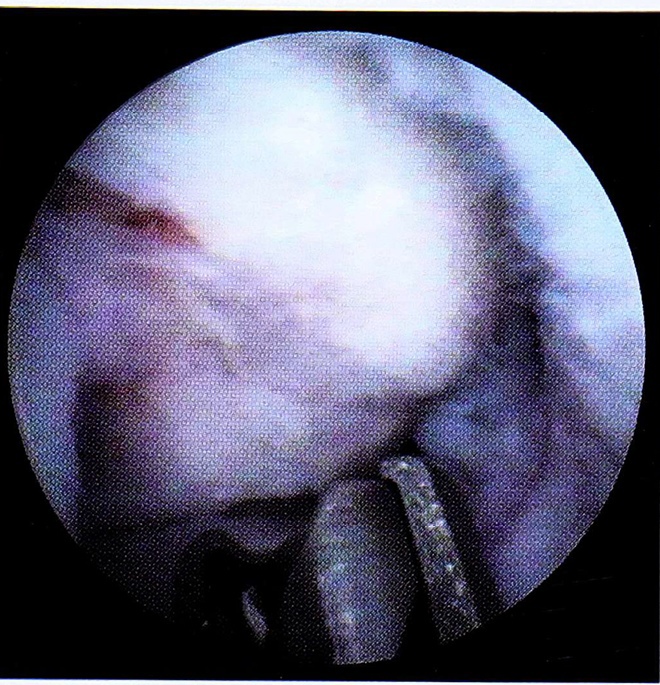

Рис. 7. Шейвирование суставной поверхности.

Используя основные и дополнительные артроскопическиедоступы,, мы получили возможность во всех случаях визуализировать все внутрисуставные структуры,, уточнить ложализащию и степень внутрисуставных повреждении и провести оперативное лечение с помощью артросжопической техники.. Были выполнены следующие виды оперативного лечения: удаление внутрисуставных тел, шейвирование участков повреждения хряща с целью удаления детенержттпвно-виененной хрящевой ткани и сглаживания суставных поверхностей, иссечение множественных посттравматических спаек (рис.. 6-8).